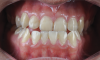

Fig 10. Postsurgical orthodontics for bite settling after the surgical procedure. Surgery for this patient consisted of maxillary surgical advancement, mandibular surgical asymmetric setback, and genioplasty (chin correction). Note the anterior and posterior crossbite was corrected and a class I occlusion was obtained.

Figure 10